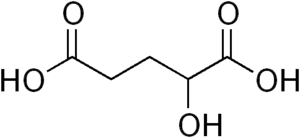

| Alpha-Hydroxyglutaric acid | |

It is associated with L2HGDH, which encodes L-2-hydroxyglutarate dehydrogenase.[5] L-2-hydroxyglutarate is produced by promiscuous action of malate dehydrogenase on 2-oxoglutarate, and L-2-hydroxyglutarate dehydrogenase is an example of a metabolite repair enzyme that oxidizes L-2-hydroxyglutarate back to 2-oxoglutarate.[6]